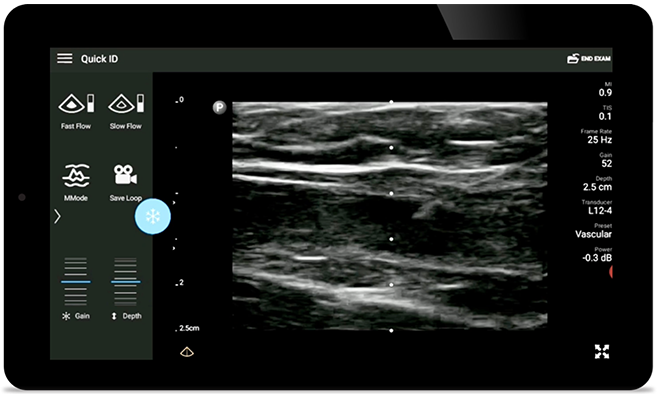

La guía por ultrasonido en tiempo real puede mejorar la precisión y la seguridad de las inserciones de CVC.

• Rango extendido de frecuencias de operación entre 12 y 4 MHz • Tamaño de apertura: 34 mm • 2D, Doppler orientable a color, Modalidad M, XRES avanzado e imágenes armónicas multivariables, SonoCT • Imágenes de alta resolución para aplicaciones superficiales: tejidos blandos, vasculares, superficiales, musculoesqueléticos y pulmonares • Marcador de línea central • Transductor USB-C con cable reemplazable